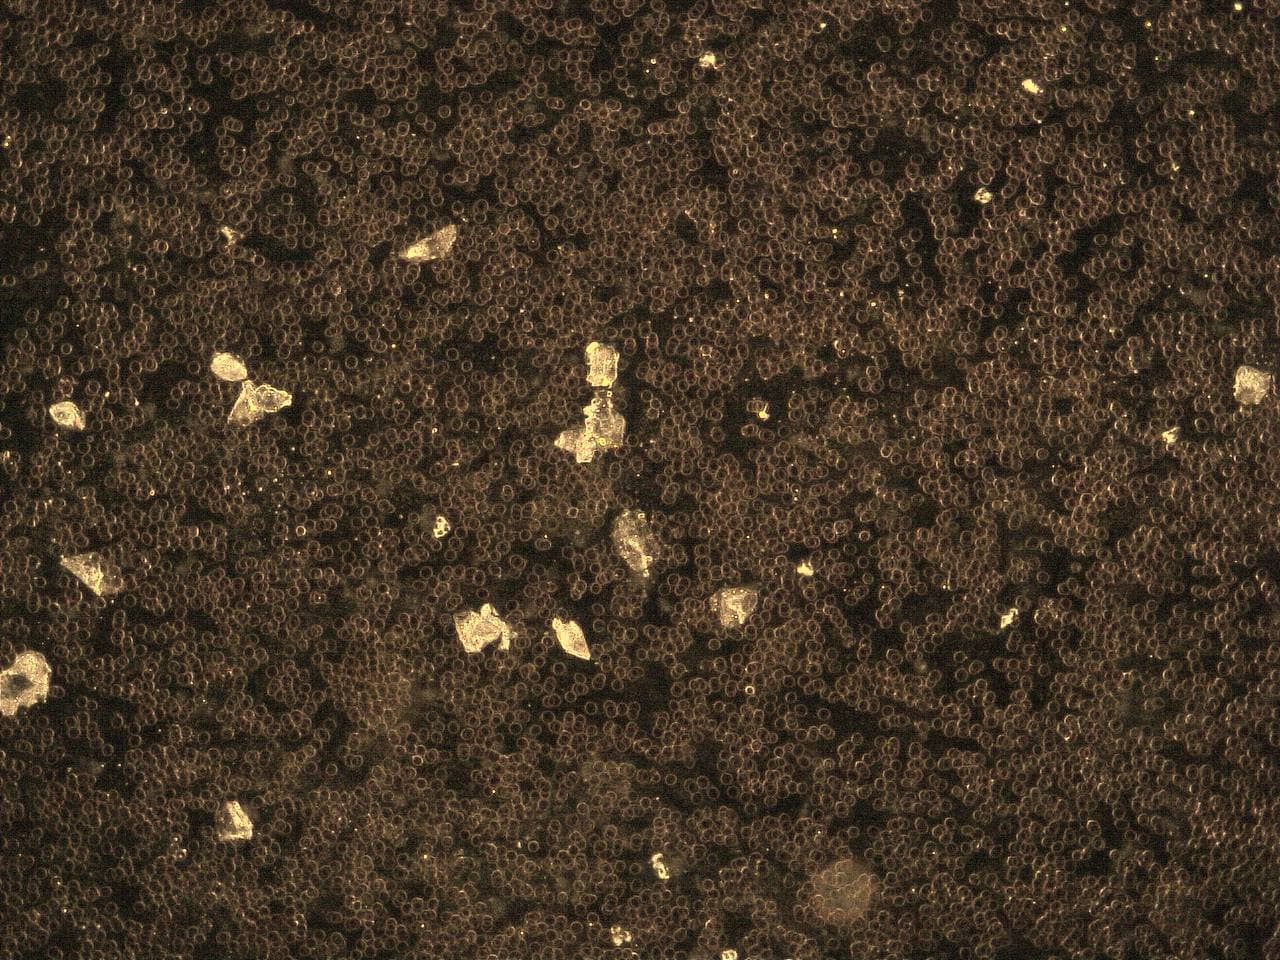

GENimpfschaden

im Blutbild einer GENgeimpften Person

15.9.2021: 9 Fotos

Impfschäden Schweiz

Coronaimpfung, [15.09.21 13:19]

https://t.me/Impfschaden_Corona_Schweiz/21521

[Weitergeleitet aus Holger Fischer

Rechtsanwalt (Maya Stella)]

Im folgenden wieder Blutbilder von Blut von

Geimpften, mit Verunreinigungen

(Dunkelfeldmikroskopie) |

GENimpfschaden

im Blutbild 15.9.2021: Foto 1

Impfschäden Schweiz Coronaimpfung, [15.09.21

13:19]

https://t.me/Impfschaden_Corona_Schweiz/21522

[Weitergeleitet aus Holger Fischer Rechtsanwalt

(Maya Stella)]

Scheibenartiges Gebilde mit leuchtenden Punkten

GENimpfschadne im Blutbild 15.9.2021: Foto 1

[37] |